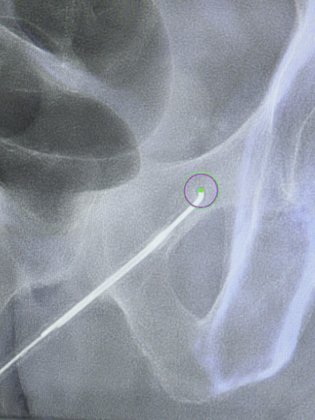

Sous guidage par imagerie (échographie, scanner ou cone-beam CT), la sonde est placée avec précision, sans incision ni cicatrice visible.

Sous contrôle d’imagerie (échographie, scanner ou cone-beam CT), le radiologue positionne une fine sonde au contact du nerf ciblé. Une fois en place, la sonde est refroidie par un gaz réfrigérant (protoxyde d’azote ou dioxyde de carbone), ce qui provoque la formation d’une petite « boule de glace » (ice ball) à son extrémité. Cette zone froide atteint –70 à –90 °C et bloque la conduction nerveuse. La phase de congélation dure quelques minutes et peut être répétée plusieurs fois si nécessaire.